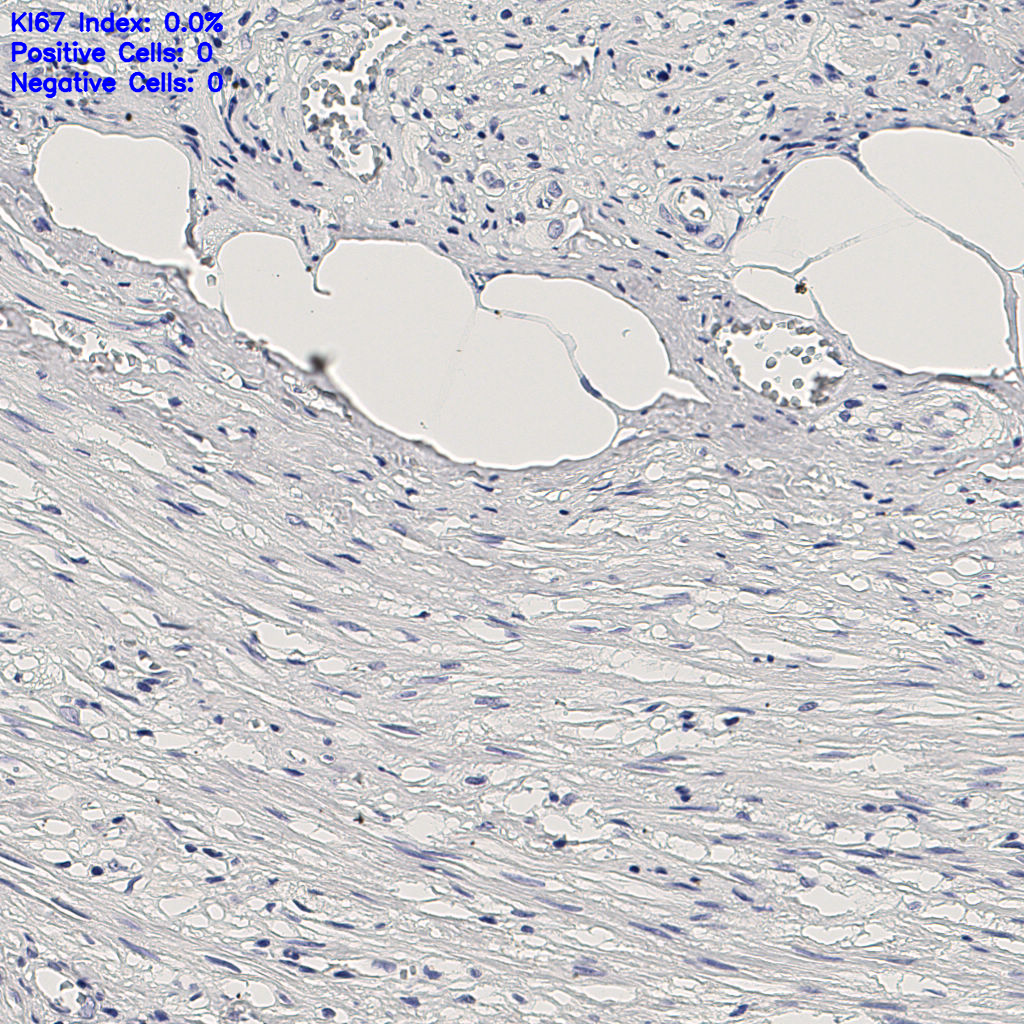

缩略图

slice_7_20_x6272_...

标记后

标记前